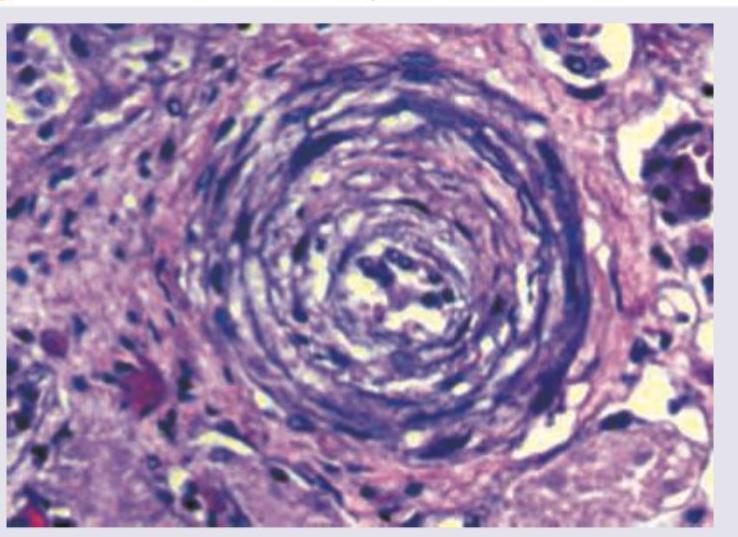

A 62-year-old man presented in the medical emergency with complaints of severe headache and dizziness. His blood pressure was recorded to be 200/146 mm Hg. Pathological slide presentation is given in the image below. What is the most likely diagnosis?

The image shows presence of:

Explanation: ***Hyperplastic arteriolosclerosis*** - The patient's severe hypertension (200/146 mm Hg) is characteristic of a **hypertensive crisis**, which is the typical setting for hyperplastic arteriolosclerosis [2]. - This condition is characterized by **concentric, laminated thickening of arteriole walls** (onion-skinning) due to proliferation of smooth muscle cells and reduplication of the basement membrane, often leading to luminal narrowing [1][2]. *Hyaline arteriolosclerosis* - This condition is typically associated with **benign hypertension** or diabetes, not the severe, acute hypertension seen in this case [2]. - It involves a **homogenous, pink, hyaline thickening** of arteriole walls due to plasma protein leakage and increased extracellular matrix, without the prominent cellular proliferation. *Accumulation of plasma proteins in the vessel wall* - While plasma protein accumulation does occur in hyaline arteriolosclerosis, it is a **component of the change**, not the primary diagnosis for the described severe hypertension and likely histological appearance. - This description is too general and does not capture the specific cellular and structural changes seen in severe hypertensive vasculopathy. *Neutrophilic infiltration* - **Neutrophilic infiltration** is characteristic of acute inflammation or vasculitis, such as in conditions like polyarteritis nodosa or ANCA-associated vasculitis. - It is **not a feature of hypertensive arteriolosclerosis**, which is a non-inflammatory vascular change due to chronic or severe pressure stress. **References:** [1] Kumar V, Abbas AK, et al.. Robbins and Cotran Pathologic Basis of Disease. 9th ed. The Kidney, p. 945. [2] Kumar V, Abbas AK, et al.. Robbins and Cotran Pathologic Basis of Disease. 9th ed. Diseases of Infancy and Childhood, pp. 498-499.

Explanation: ***Monckeberg arteriosclerosis*** - This condition is characterized by **calcification of the media of muscular arteries**, without significant luminal narrowing. - It is often an incidental finding on imaging or autopsy and is typically **non-obstructive**. *Atheroma* - An atheroma is a **plaque** formed within the arterial wall, primarily composed of **lipids, inflammatory cells, smooth muscle cells, and fibrous connective tissue**. - It leads to **luminal narrowing** and can cause ischemia or thrombosis. *Hyaline arteriosclerosis* - This involves **homogenous, amorphous, pink hyaline thickening of the arteriolar walls** [3], often seen in benign hypertension and diabetes. - It results from **plasma protein leakage** across damaged endothelial cells and increased extracellular matrix production. *Hyperplastic arteriosclerosis* - Characterized by **"onion-skin" concentric thickening of arteriolar walls** due to smooth muscle cell proliferation and reduplication of the basement membrane [1][2]. - It is typically associated with **severe or malignant hypertension** [1] and can lead to luminal obliteration. **References:** [1] Kumar V, Abbas AK, et al.. Robbins and Cotran Pathologic Basis of Disease. 9th ed. Diseases of Infancy and Childhood, pp. 498-499. [2] Kumar V, Abbas AK, et al.. Robbins and Cotran Pathologic Basis of Disease. 9th ed. The Kidney, p. 945. [3] Kumar V, Abbas AK, et al.. Robbins and Cotran Pathologic Basis of Disease. 9th ed. The Kidney, pp. 943-945.